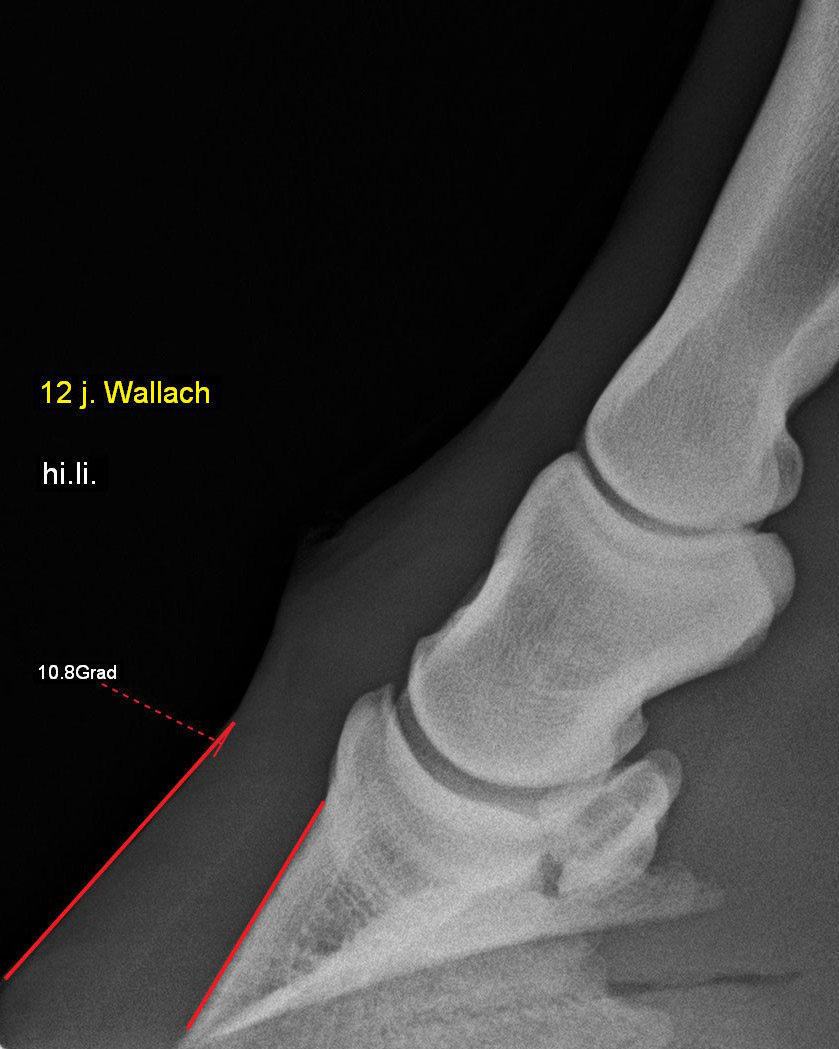

Pferd mit Hufrehe - Hufbeinrotation 10,8°